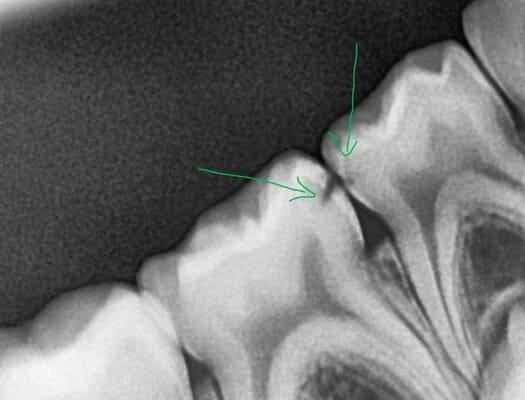

Поява перших постійних зубів, а це шості зуби, відбуваються, коли дитина ще не може, як слід провести їх гігієну та попіклуватись про їх здоров’я. Тому, на жаль вони і вражаються карієсом досить швидко. Пацієнт ще маленький – 6 років, а лікування потребує дорослого: зі знеболенням та ізоляцією. Саме таке і було проведене в даному випадку: зуб очищений від інфікованих тканин, відновлений фотополімерним матеріалом і готовий довго служити юному господарю.